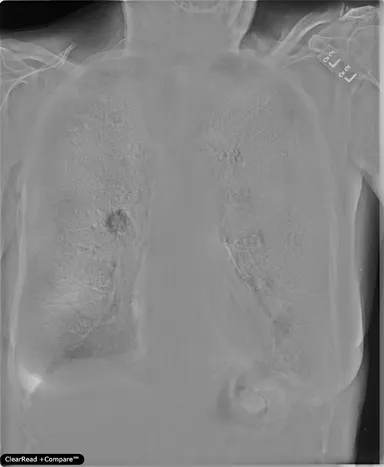

・胸部X線経時差分ソリューション/ClearRead +Compare※1

「ClearRead BS」にさらなる画像処理技術を搭載。同一患者の現在と過去の画像から骨組織を透過させるとともにその差分を抽出し、経時的変化部分を強調した画像を生成する。

・「ClearRead +Compare」:胸部X線経時差分ソリューション

- 肺組織の視認性を大きく向上。骨組織透過処理、経時差分画像を生成

- 胸部X線画像上の病変の見落とし防止、気づきの促進

- 読影時の医師の心的負担を軽減

- 国内外あらゆる胸部X線装置で撮影された画像に対応